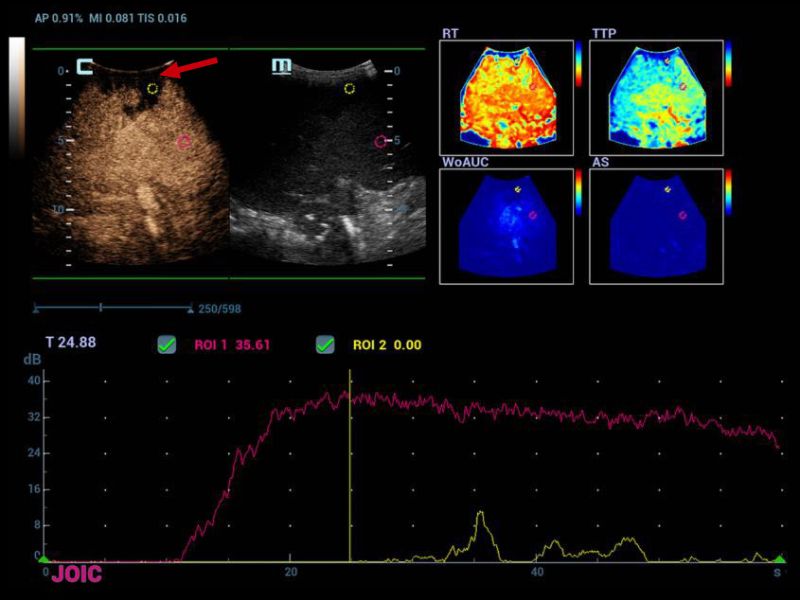

Hypoperfusion zone in segment 8/7 in wedge morphology (red arrow), in the perfusion curves the ROI located in that segment does not show an enhancement of

Figure 4. Hypoperfusion zone in segment 8/7 in wedge morphology (red arrow), in the perfusion curves the ROI located in that segment does not show an enhancement of